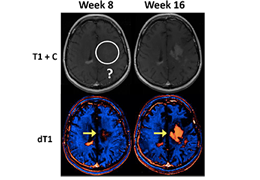

ART-Plan™ Artificial Intelligence Contouring